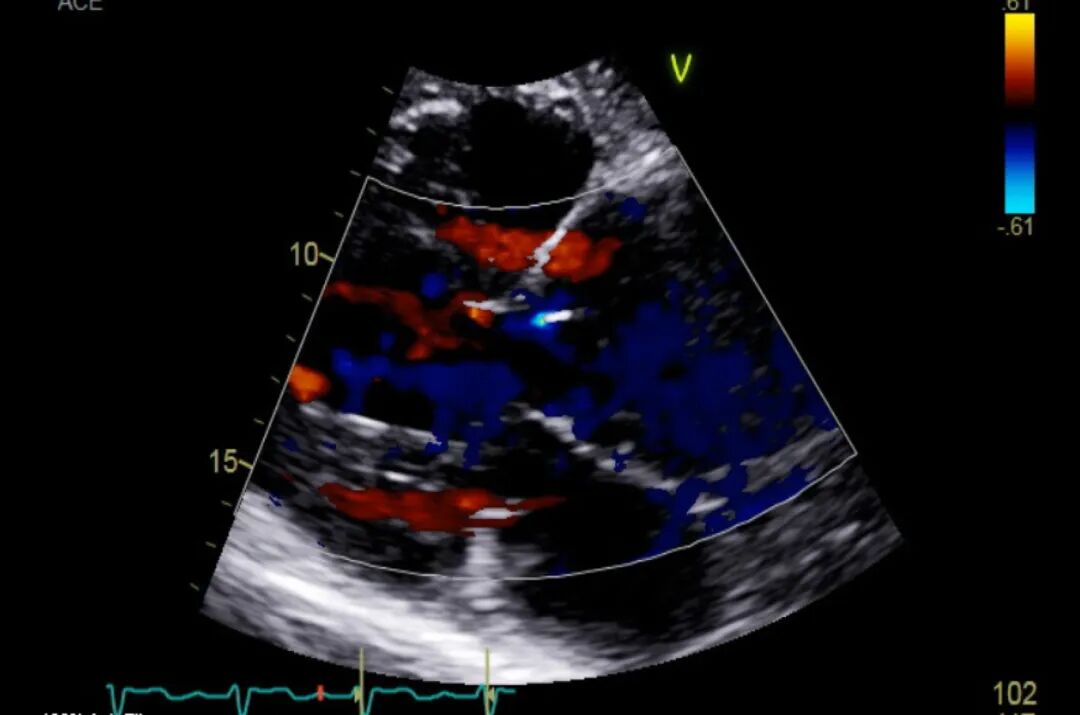

图2 TTE胸骨旁长轴视图彩色多普勒

TTE显示重度主动脉瓣反流。主动脉瓣叶显示不清。主动脉根部严重扩张,直径达 6.5 cm。升主动脉严重扩张,直径为 6.2 cm。